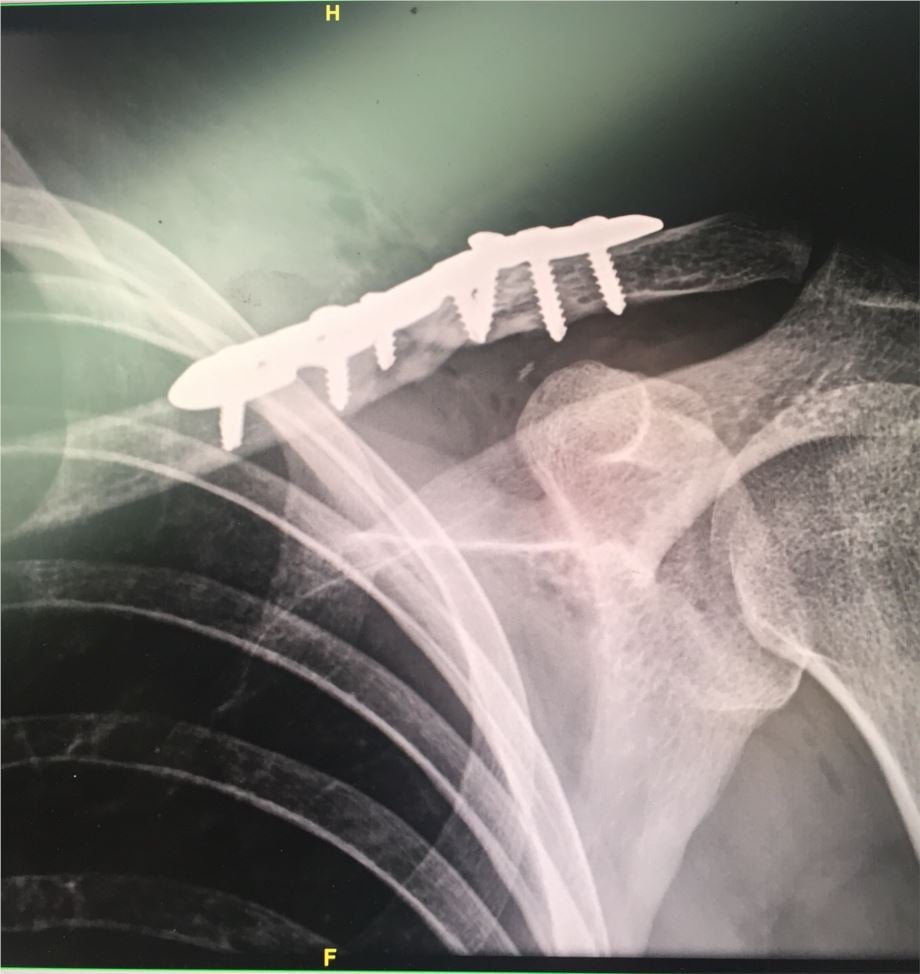

Tak wyglądał obojczyk zaraz po operacji: